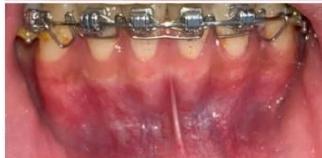

Figure 2: Pre-Treatment Intraoral Photographs

Intraoral examination revealed severe proclination and protrusion of both the maxillary and mandibular incisors [6]. The occlusal relationship was Class I at the canine (tooth 3) and first molar (tooth 6) levels bilaterally. A critical unfavorable biological factor was the proximity of the mandibular incisor roots to the labial cortical plate, representing a high-risk condition when planning extraction-based anterior retraction mechanics [10-12]. All four third molars were present.